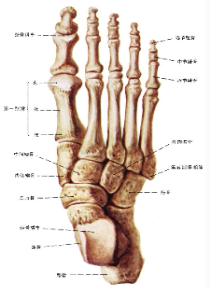

足骨

包括跗骨、跖骨和趾骨。跗骨共7块,分前、中、后列。后列包括距骨和跟骨;中列为距骨前方的足舟骨;前列为内侧楔骨、中间楔骨、外侧楔骨及跟骨前方的骰骨

跖骨,共5块,近端为底,与跗骨相接;中间为体,远端称头,与近节趾骨底相接

趾骨,共14块,踇趾为2节,其余各趾为3节。分为近节趾骨,中节趾骨和远节趾骨。每节趾骨近端为底,中间部为体,远端为滑车